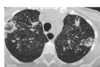

Consolidação em lobo superior direito com áreas de cavitação

Padrão de micronódulos centrolobulares com árvore em brotamento

TB pós primária.